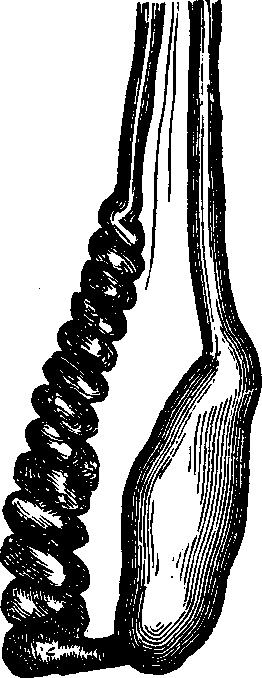

Generation. So long as the vital principle remains in the sperm-cell, it lies dormant. That part of the cell which contains this principle is called the spermatozoön, which consists of a flattened body, having a long appendage tapering to the finest point. If it be remembered that a line is the one-twelfth part of an inch in length, some idea may be formed of the extreme minuteness of the body of a human spermatozoön, when we state that it is from 1/800 to 1/600 part of a line, and the filiform tail 1/50 of a line, in length. This life-atom, which can be discerned only with a powerful magnifying glass, is perfectly transparent, and moves about by executing a vibratile motion with its long appendage. Within this speck of matter are hidden the multifarious forces which, under certain favorable conditions, result in organization. Magnify this infinitesimal atom a thousand times, and no congeries of formative powers is perceived wherewith to work out the wonders of its existence. Yet it contains the principle, which is the contribution on the part of the male toward the generation of a new being.

Fig. 1. A. Human

Spermatozoön magnified about 3,800 diameters. B. Vertical and

lateral views of spermatozoa of man. C, D, E, F. Development of

spermatozoa within the vesicles of evolution. G. Cell of the sponge

resembling a spermatozoön. H. Vesicles of evolution from the

seminal fluid of the dog in the parent cell I. Single vesicles of

different sizes. J. Human spermatozoön forming in its cell.

K. Rupture of the cell and escape of the spermatozoön.